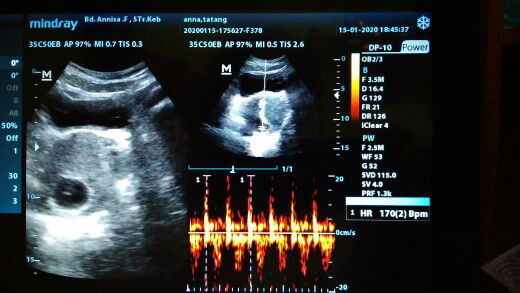

USG pertama